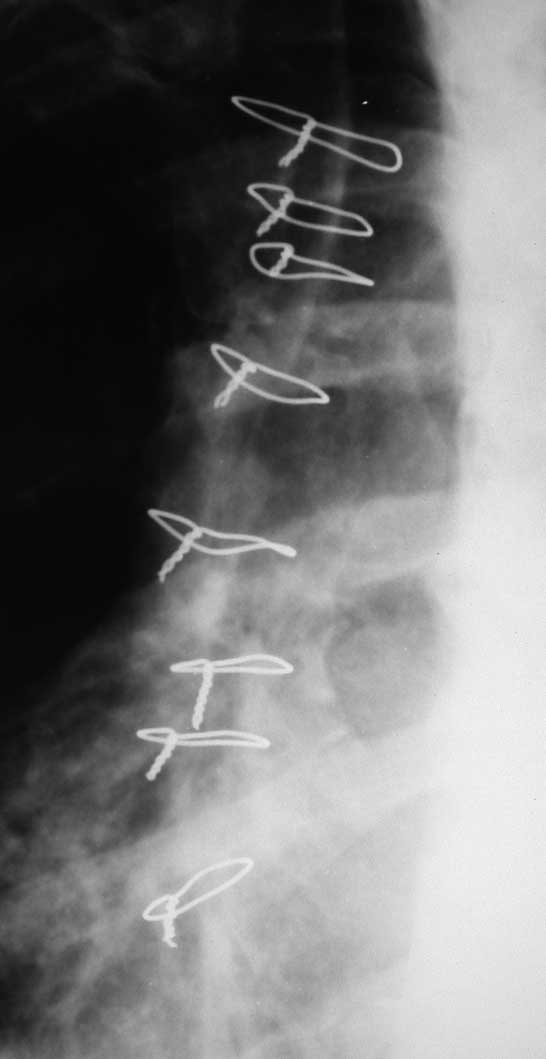

Добрый вечер, уважаемые Коллеги! Хочу поделиться опытом лечения ложных суставов грудины, осложнённых хроническим остеомиелитом. Все пациенты после аортокоронарного шунтирования. Фиксация грудины осуществлялась лавсановыми нитями. Основная проблема заключается во флотации грудины и необходимости применения аппаратов внеочаговой фиксации. Предложенный аппарат прост и состоит из комплектующих аппарата Илизарова и эндокорректора позвоночника Роднянского -Гупалова (именно крючки,которые фиксируются за дужки позвонков при сколиозе). Крючки вводятся в тело грудины посредством инструментов, которые предназначены для установки эндокорректора. Аппарат позволяет дать нужную компрессию, исключить флотацию и добиться сращения грудины. Предварительно делается полноценная санация очага остеомиелита. В одном случае производилась костная аутопластика из гребня подвздошной кости - был большой диастаз.

Опыт оперативного лечения то же небольшой - оперировл троих пациентов по данной методике.

У всех удалось добиться сращения грудины и заживления раны. Фиксация аппаратом осуществлялась до 3-х месяцев.